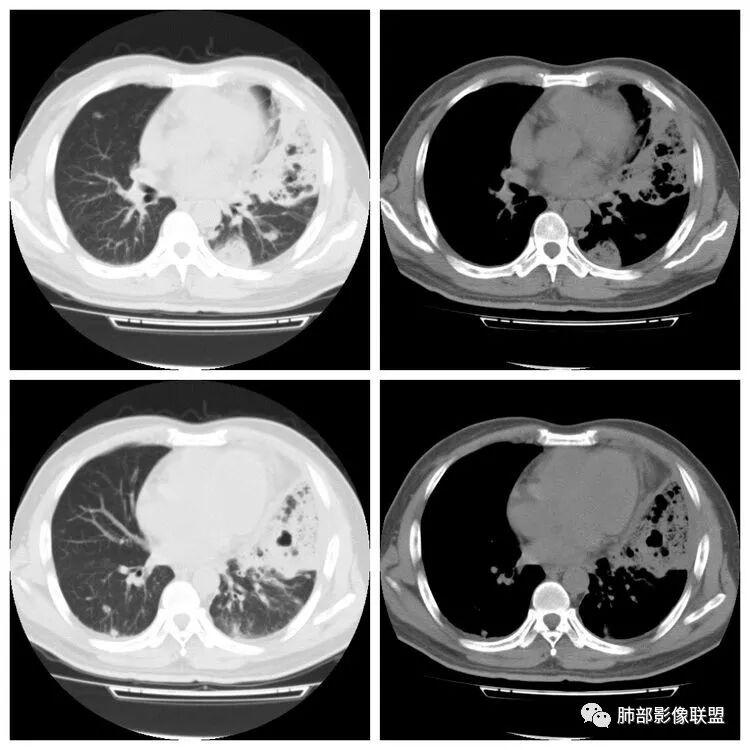

胸 CT

南边:胸膜下,类圆形,边界清,内有坏死,典型的反晕征,支气管壁增厚不明显,支持血道来源脓毒栓子所致梗死、感染

血道来源没问题

左下叶大片类似病灶

下面是一例几乎一样的肺克:

南边:反晕征是毛霉菌的特点按理单从影像:毛霉菌更多符合因为细菌性的特点:液气平面,囊,这个没出现

肺克的影像表现(唐绍宏总结):分布:单侧上叶病变,以右肺上叶多见;患者长期卧床则双脚下肺后基底段分布(国外下肺多见,可能与平均寿命长,卧床及住托老机构多有关) ;如多叶段病变,则以肺上叶后段或下叶后基底段为最明显形态:气管壁增厚、磨玻璃、小叶实变、节段实变、大叶实变,坏死小空洞(直径小于2cm) ,少量胸腔积液50%、脓胸20%特点:早期气管壁增厚较明显、广泛,越靠近病灶越明显,越靠近肺门越明显,见于实变病灶外,偶尔见于磨玻璃影内(支气管通气征) ;未经抗生素治疗,实变病灶内无支气管通气征;早期即可出现坏死,无论坏死还是空洞,绝大多数直径小于2cm (可能与此菌有厚夹膜有关,参考隐球菌)